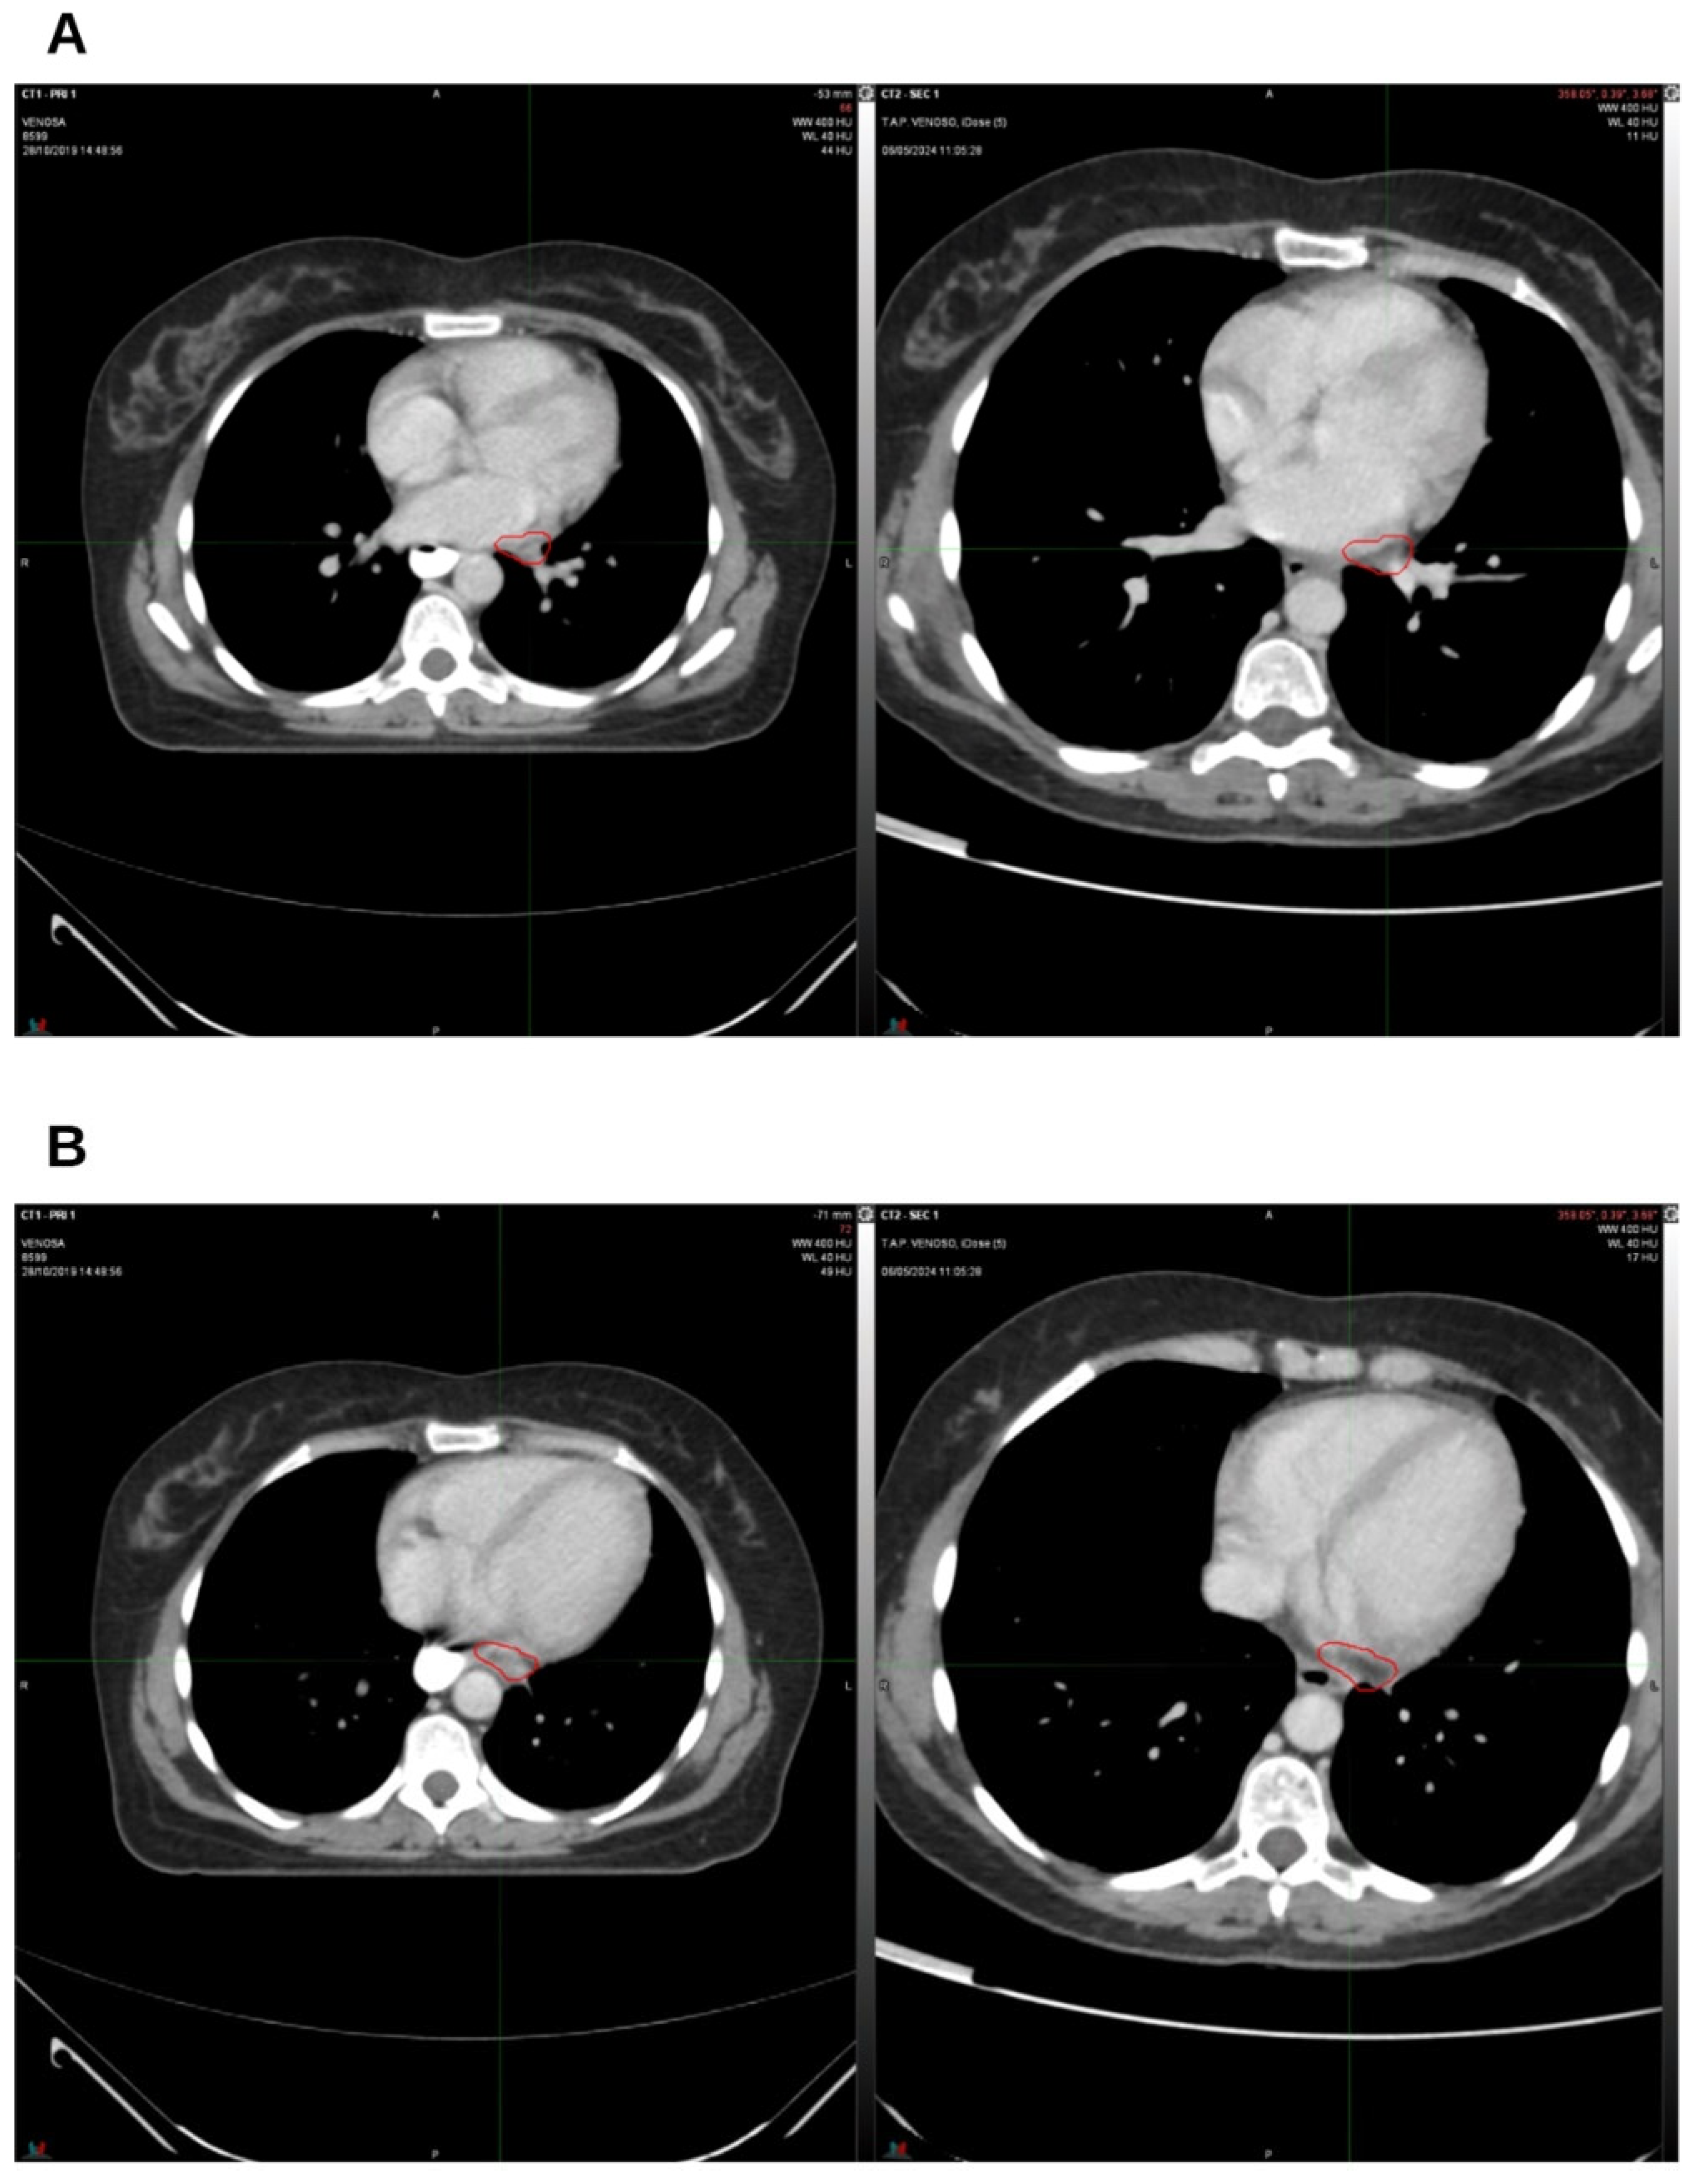

2. Case Presentation